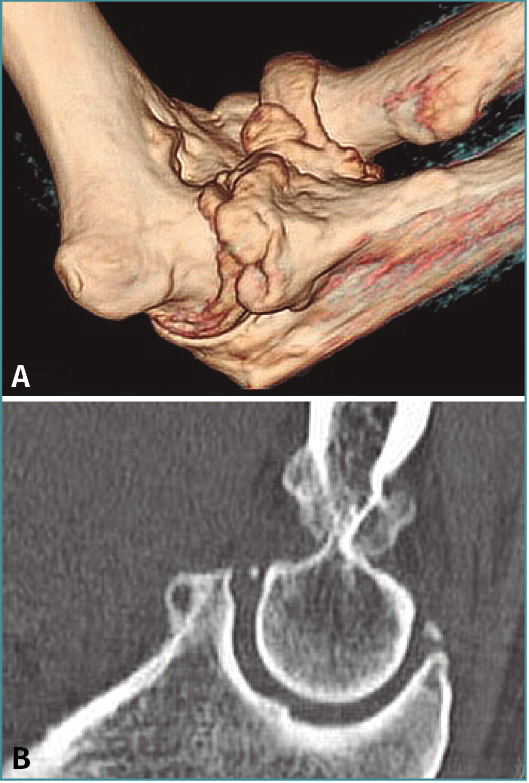

En todos los casos hemos solicitado una tomografía axial computarizada (TAC) 3D previa a la intervención, lo que es de gran utilidad para preparar la cirugía y saber dónde y cuántos osteofitos y cuerpos libres vamos a resecar (Figuras 1 y 2; Vídeo, minutos 0-1:36).

Figura 1. A: tomografía axial computarizada bidimensional (TAC); B: TAC 3D para valorar la presencia, el tamaño y la localización de osteofitos y cuerpos libres.